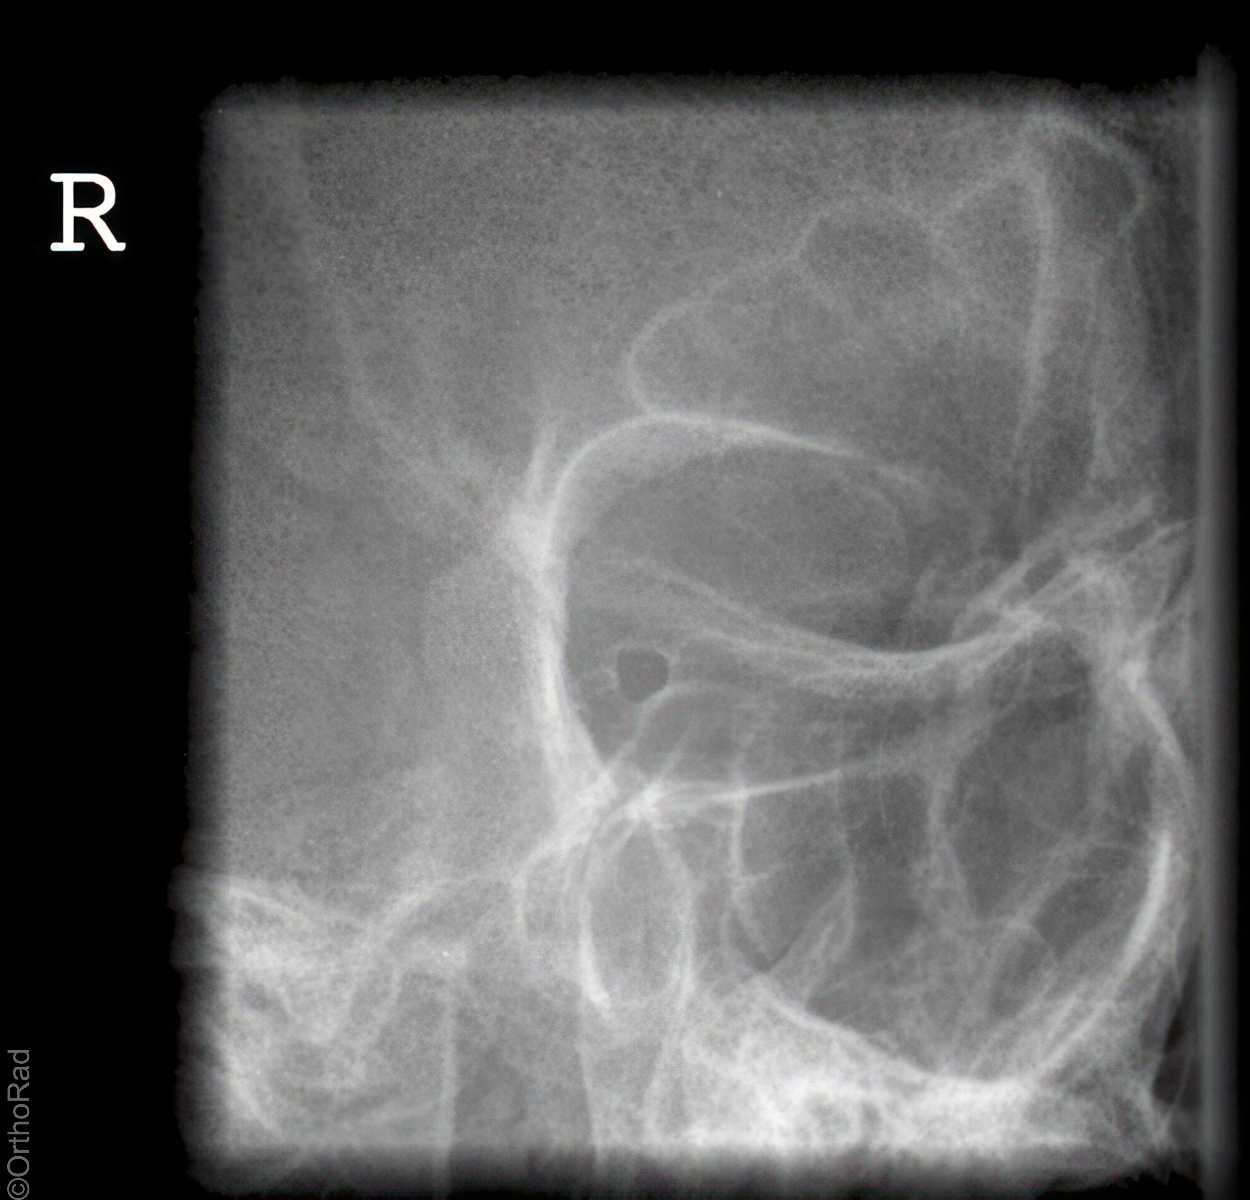

Unterkiefer nach Clementschitsch

Technik

• FDA: 1,15 m

• Ausgangsformat: 18/24 hoch

• mit Raster

• Röhrenkippung: 15° caudo-cranial

Lagerung

sitzt aufrecht und gerade mit dem Gesicht zum Stativ

Kopf gerade

Kinn stark anziehen lassen

Stirn dem Stativ anliegt

Mund maximal öffnen

Zentralstrahl

Im Winkel von mindestens 15° caudo-cranial okzipitomental. Längsstrahl verläuft durch die Medianebene. Querstrahl unterhalb des Occiputs auf Nasenwurzel. Achtung! Bei Röhrenkippung auf Zentrierung achten.

Anmerkung

Vollständige Darstellung des Unterkiefers und gute Beurteilung der Kiefergelenke. Bei Kiefergelenk Fragestellung:

1. Aufnahme mit geöffneten Mund

2. Aufnahme mit geschlossenem Mund

Qualitätskriterien

Übersichtliche Darstellung des gesamten Unterkiefers mit seitengleich gut einsehbaren Kiefergelenken